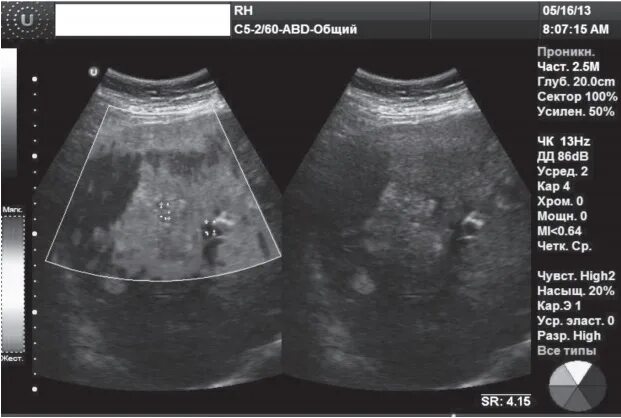

Как лечить фиброз 3